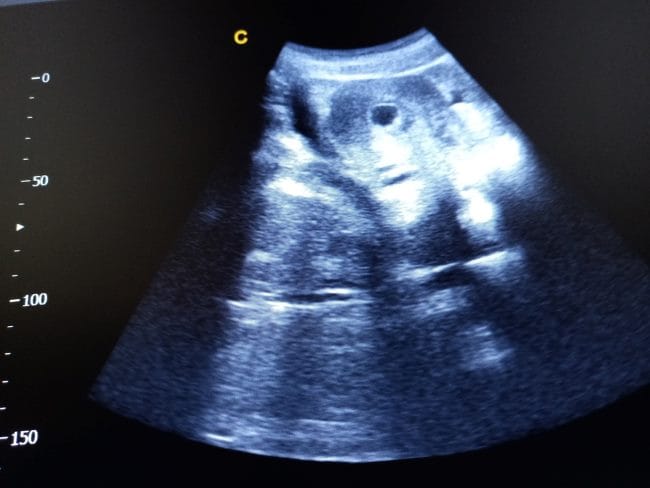

Di usia kehamilan 6 minggu, perkembangan kantung janin cukup pesat, Bun. Bila pada usia 4 minggu ukurannya masih sekitar 2 mm, kantung janin pada minggu ke-6 sudah membesar hingga sekitar 6 mm, yaitu seukuran kacang kedelai. Pertumbuhan ini menunjukkan kehamilan Bunda berlangsung sebagaimana mestinya, serta tubuh Bunda sedang mempersiapkan ruang yang aman bagi Si Kecil.

Melalui USG, kantung janin 6 minggu juga sudah memperlihatkan 2 struktur penting, yaitu kantung kuning telur (yolk sac) dan embrio. Kantung kuning telur berfungsi utama menyalurkan nutrisi, oksigen, dan darah dari Bunda ke embrio sebelum plasenta terbentuk sempurna. Dengan begitu, embrio bisa tumbuh dan terbentuk menjadi janin.

Kehadiran kantung kuning telur dan embrio yang tampak jelas pada hasil USG menjadi salah satu tanda bahwa kehamilan Bunda sehat dan normal. Tanda-tanda ini membawa kabar baik sekaligus menenangkan hati banyak calon ibu, karena perkembangan janin berjalan sesuai harapan di awal kehamilan.